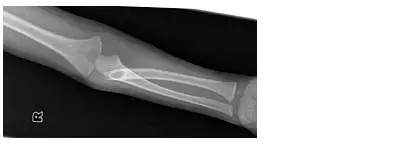

2 歲男孩因右上肢活動受限,被父母帶來求診,右肘部的 X光檢查結果如附圖,該男孩右上肢活動受限最嚴重的是下列何種動作?

本題考查兒童肘關節骨折脫位的影像學辨識與功能受限判斷。X 光顯示右肘部 Monteggia 骨折脫位(Monteggia fracture-dislocation),為兒童常見的肘部複合損傷,表現為近端尺骨骨折合併橈骨頭(radial head)脫位,直接影響前臂旋轉功能。

圖一(側位 X 光): 肘關節側位影像可見橈骨頭明顯向前移位,偏離正常與肱骨小頭(capitellum)的對位關係(radio-capitellar line 中斷)。近端尺骨可見骨折線,整體呈現前方橈骨頭脫位合併尺骨骨折的典型 Monteggia 第一型(Bado Type I)外觀。

圖二(前後位 X 光): 前後位影像清楚顯示橈骨頭自肱骨小頭之正常關節面脫出,移位至前外側。橈骨與尺骨的排列關係明顯異常,近端至中段尺骨可見骨折,進一步確認 Monteggia 骨折診斷。此影像為辨認橈骨頭脫位方向的關鍵視圖。